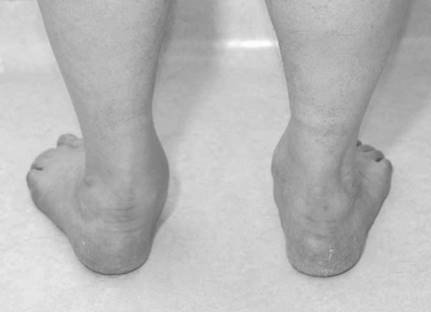

Describe this picture?

This is a picture of a plano-valgus foot. There is the โtoo many toesโ sign. Pes planus can be congenital or acquired. The commonest cause of adult acquired fl at foot is tibialis posterior tendon dysfunction (TPTD). The tibialis posterior is the main inverter of the hindfoot. It also acts as an elevator of the midfoot (sling) as it inserts into the navicular, plantar cuneiforms, and second, third, and fourth metatarsal (MT) bases.

The condition is most often seen in middle-aged women whose body morphology, aided by gravity, tests the tendon as it is starting to age.

What are the stages of this condition and how are they managed?

The tendon can become infl amed, painful, and swollen. The foot does not initially change shape and patients are still able to do a single leg tiptoe raise, although they quickly fatigue (Johnson Stage 1). Some patients settle with enforced rest in a supportive brace or cast.

As the tendon degenerates it lengthens. The foot changes shape with the hindfoot going into valgus. Patients are no longer able to do a single leg tiptoe raise. (Often the pain over the tib post may have settled, especially if the tendon has completely ruptured.) If the hindfoot is still fl exible (Johnson Stage 2), this can be treated with orthotics to help support the foot and medial arch or by surgery. Surgery involves reinforcing the tibialis posterior tendon (TPT) with a fl exor digitorum longus (FDL) tendon transfer. This reconstruction is then protected by bringing the hindfoot into neutral alignment with a medial sliding calcaneal osteotomy. The Achilles tendon occasionally needs to be released (percutaneously), as if the hindfoot has been in valgus for some time it will have tightened preventing full correction to neutral.

I f the valgus hindfoot deformity is fi xed (Johnson Stage 3) reconstruction is not achievable. The subtalar joint is degenerate. Surgical treatments involve a talo-navicular and subtalar fusion or a formal triple arthrodesis.

M yerson added a fourth stage when the deformity led to signifi cant ankle arthritis secondary to valgus strain.